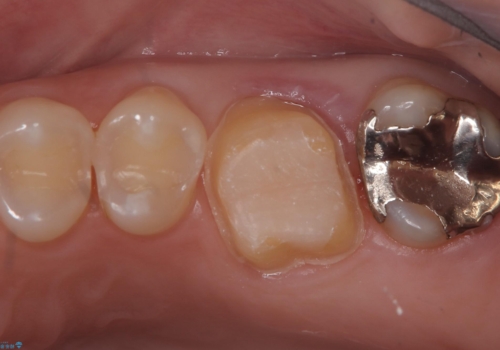

- 主訴:銀の詰め物を白くしたい

保険メタルインレーの入っている歯に虫歯が認められたため、セラミッククラウンでのやり替えとなりました。

保険のメタルインレーを白くしたいということで来院されました。

左上6の近心にカリエスを認め、残存歯質と破折リスクの観点からセラミッククラウンでのやり替えとなりました。